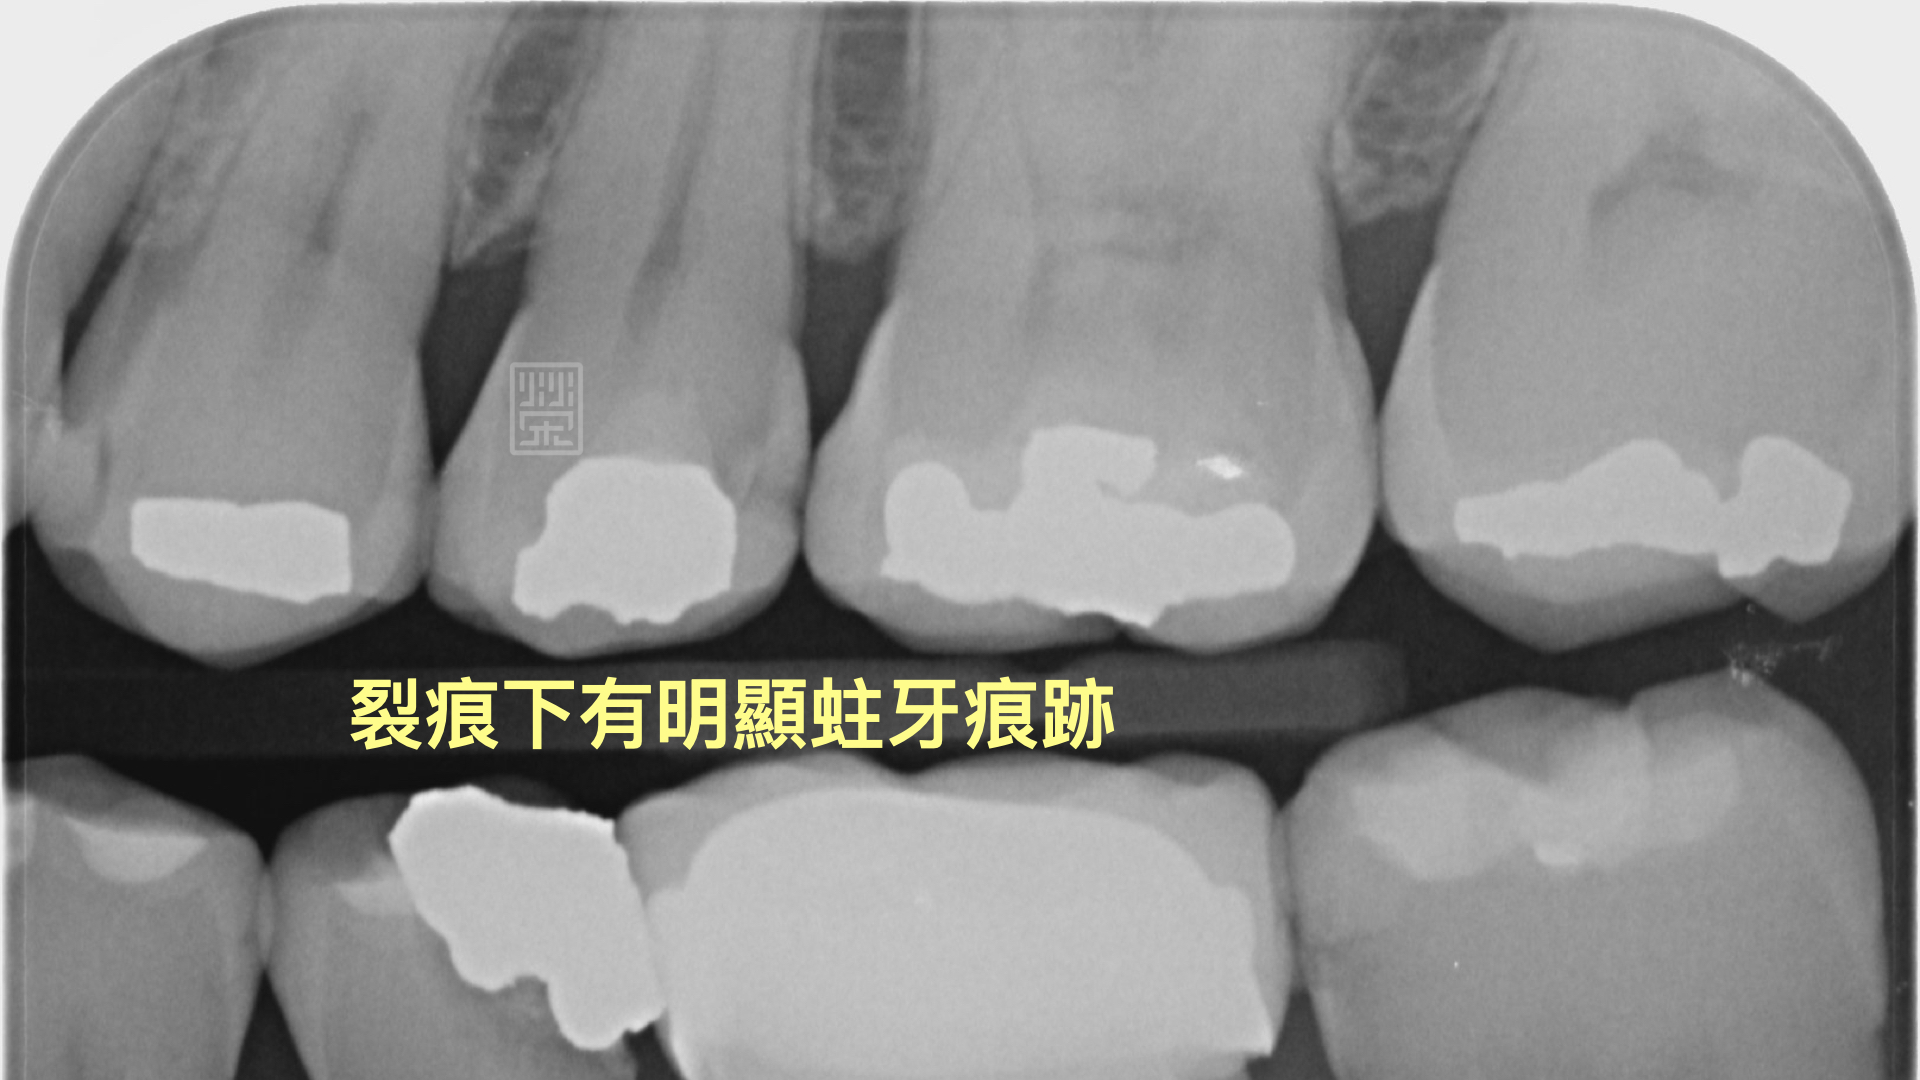

牙齒旁邊有裂痕

裂痕相對位置下的X光片,可以明顯發現蛀牙